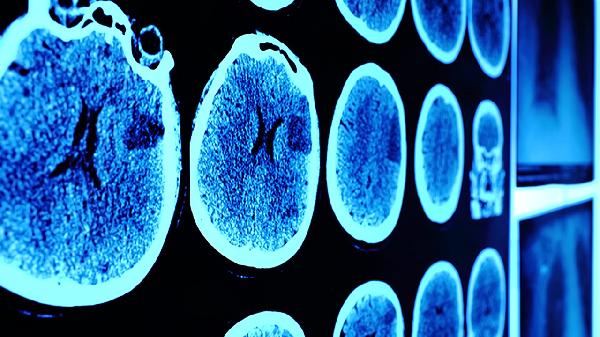

脑震荡患者除药物治疗外,急性期需卧床休息1-3天,避免剧烈活动和电子屏幕刺激。饮食宜选择富含优质蛋白和维生素B族的食物如鸡蛋、瘦肉、全谷物等,促进神经修复。恢复期可进行散步等低强度运动,但需避免头部再次受伤。若出现持续呕吐、意识模糊等症状应立即就医复查头颅CT。